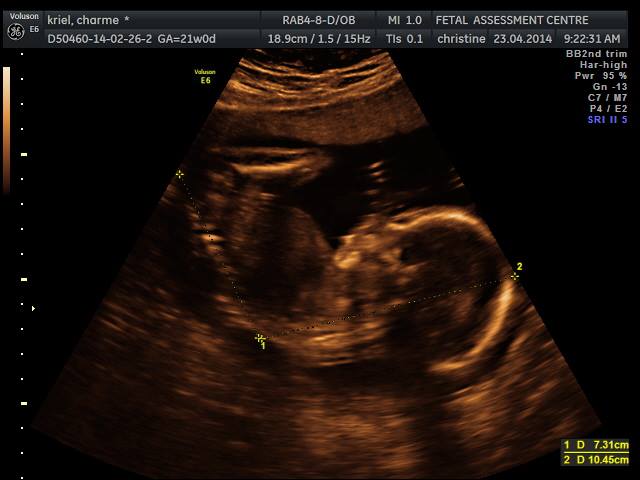

10247392_10154143455355179_7329365009743144948_nMy vriende het hierdie bondeltjie in my maag Peanut gedoop en later het ons besluit dat aangesien dit net ‘n Blob is…sy naam Bob the Blob gaan wees. Ek het myself nog altyd as meer van ‘n seuntjie ma gesien en ek was vasoortuig dat dit ‘n seuntjie is. Op 13 weke vind ek met skok uit ons bondeltjie liefde is toe al die tyd ‘n dogtertjie. En so verander Bob na Blobina. Ek hou glad nie van pienk nie…so dit het my ‘n hele tydjie gevat om gewoond te raak aan die idee. Ek het selfs nagmerries gekry waar ek haar hele kamer pienk geverf het en pienk fluffy kussings oral. Dankie Vader dit was net ‘n droom.

Op 27 weke, Maandag 8 Junie, het ek ‘n gewone opvolg afspraak by die ginekoloog gehad. Hy het my die vorige keer belowe dat hy ‘n ekstra scan sal doen aangesien my man vir die eerste keer by gaan wees vir ‘n afspraak. So kan hy ook darem vir Blobina kan sien. Ons was so opgewonde en ek kon nie wag om te sien hoe hy gaan reageer as hy haar die eerste keer sien beweeg en speel in my maag nie.